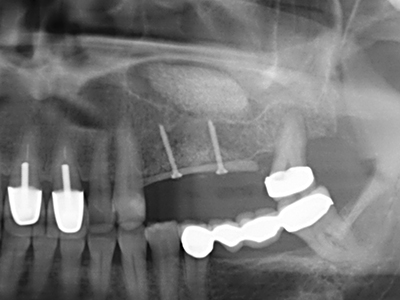

En la extracción de bloques óseos la piezocirugía también presenta ventajas adicionales: Además de la alta precisión en la osteotomía que ya se ha descrito antes, se ha comprobado que el uso de los delgados insertos de sierra resulta especialmente cuidadosas con el hueso. Frente a esto, sobre todo cuando se usan las fresas de Lindemann, cabe esperar pérdidas en la extracción significativamente más altas debido al mayor grosor de la parte frontal del cabezal (Lakshmiganthan, Gokulanathan et al. 2012). La separación basal que se necesita en particular en los injertos de bloque extraídos de forma retromolar se ve facilitada mediante sierras perpendiculares especialmente previstas a tal fin, lo que permite considerar que la cirugía piezoeléctrica es un procedimiento preciso y seguro para la obtención de bloques de hueso en el área retromolar (Happe 2007) (fig. 1-12).

Si es preciso realizar intervenciones quirúrgicas en las que el hueso está en contacto directo con estructuras sensibles, como son los vasos sanguíneos o los nervios, los instrumentos rotativos presentan un enorme potencial de provocar lesiones iatrogénicas. Así, precisamente en la representación de nervios después de una lesión iatrogénica, o en el transcurso de la lateralización de un nervio para resecciones, reconstrucciones o incorporación de implantes, los equipos piezoeléctricos pueden resultar muy útiles para preparar la tapa ósea y retirar las partes de tejido duro cercanas al nervio (fig. 17-20). Por lo general, un ligero contacto del cordón nervioso con el inserto piezoeléctrico no tiene consecuencia alguna; ahora bien, un procedimiento poco cuidadoso con movimientos tipo sierra o piezas de trabajo sobre la base ósea aún existente puede provocar lesiones nerviosas temporales o incluso permanentes. Con todo, el riesgo de sufrir una lesión de este tipo se considera significativamente inferior que en los casos en los que se utilizan sierras y fresas (Pereira, Gealh et al. 2014).